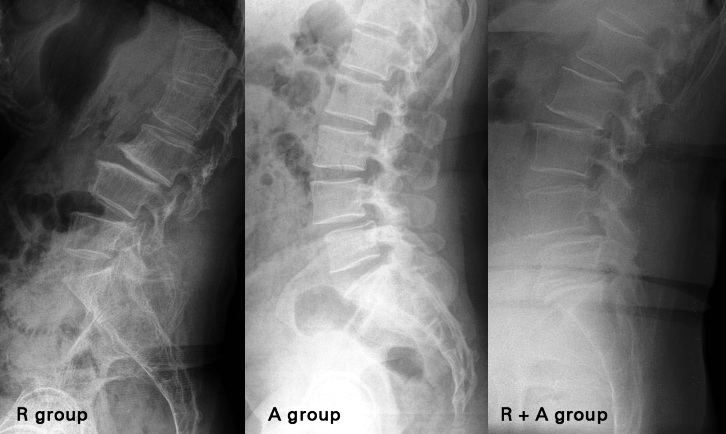

Retrolisthesis is associated with back pain and impaired back function. According to literature studies Retrolisthesis has been found to be accompanied by disc degeneration, a decrease in lumbar lordosis, decrease in vertebral endplate angle and segmental height.

Retrolisthesis is a term used to define an acute spine condition in which the backward slippage of one vertebra onto the other vertebra immediately below it takes place. Vertebrae are the bones that make up the spinal column and are separated from each other by cushioning intervertebral discs. Hence, Retrolisthesis is a posterior displacement of the vertebral body with respect to the adjacent vertebrae to a degree less than a luxation or dislocation. Retrolisthesis is seen in the cervical spine and lumbar region and also in the thoracic region.

Retrolisthesis is a degenerative or congenital condition in which the vertebra of spine gets displaced and moves backward onto the vertebra lying below it. Retrolisthesis acts as a compensatory mechanism for moving the gravity axis posteriorly for the sagittal imbalance in lumbar spine under low pelvic incidence and insufficient intra-spinal compensation .In most cases of vertebral slippage, it will involve a forward movement of an upper vertebra which will slip towards the chest.